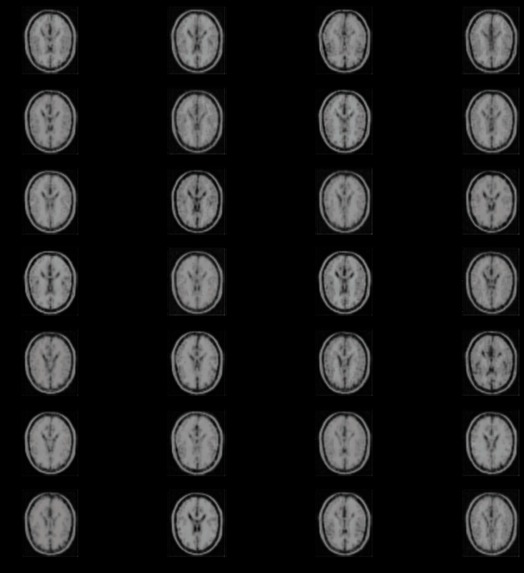

One of the main aspects of our project is MRI Image Synthesis. In this, we convert T1-Weighted images into T2-Weighted images. Along with this, our other model helps by generating Segmented Brain MRI images to show the distribution of white matter.

So we have created two models, one for Image synthesis and the other does Segmentation. Both works on generating images. We have implemented VAEs to achieve the purpose.